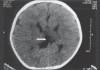

Aicardi syndrome is a rare genetic disorder. The salient features of this syndrome include agenesis of corpus callosum, chorioretinal lacunae and infantile spasms. Of these three, chorioretinal lacunae is the most constant feature present. This case highlights the importance of fundus findings by an ophthalmologist in making the diagnosis of this rare syndrome.